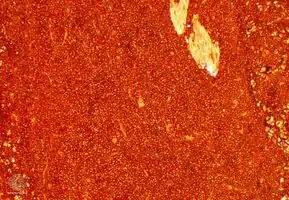

Micrograph of a plasmacytoma. -

Micrograph of a plasmacytoma. H&E stain.